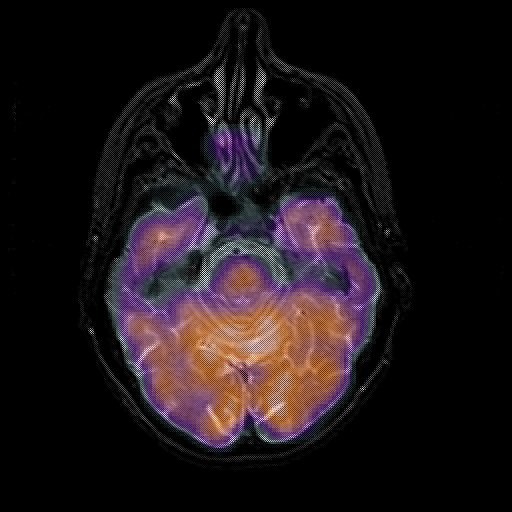

overlay 1: Slice 17

Slice 17

MRCBFCBF with

T1PDT2T1PDT2